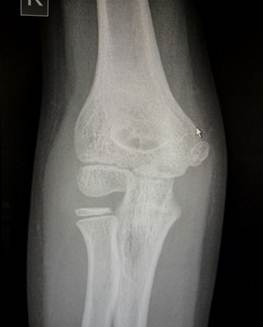

7 лет – 10 лет

В этом возрасте начинается процесс окостенения медиального вала

блока, в котором появляются мелкие, неправильной формы ядра окостенения. В 8

лет появляется ядро окостенения вершины локтевого отростка. Чуть позже к нему

добавляются мелкие ядра - спутники. К концу периода появляется ядро окостенения

латерального надмыщелка.

Возраст 7 лет. Ядро окостенения головчатого возвышения плавно

распространяется в латеральный вал блока и он начинает прослеживаться. Рядом с

ним заметно маленькое линейное ядро окостенения в медиальном вале блока. Появилось два маленьких ядра окостенения

вершины локтевого отростка.

11- 13 лет

Это возраст, в котором все ядра окостенения достигли максимального

развития и приняли формы соответсвующих образований. На рентгенограммах их

разделяют узкие полоски ростковых зон. Это максимальный расцвет детского локтя.

Возраст

12 лет. Все ядра окостенения локтя развиты и разделены узкими хрящевыми

прослойками. Вершина локтевого отростка содержит основное ядро окостенения и

ядро – спутник неправильной формы.

14 лет. Стремительное закрытие зон роста локтевого сустава. Можно заметить

узкие просветы в основании медиального и латерального надмыщелков, а также пока

еще открытую зону роста в локтевом отростке.